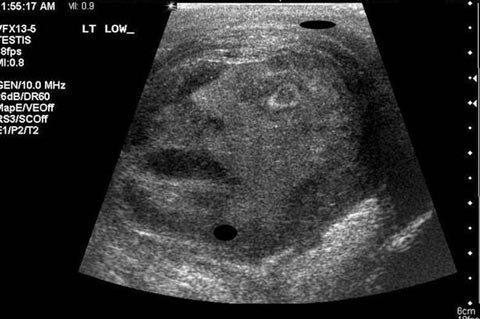

Dưới đây là một vài ví dụ được ưa thích khác của hiện tượng “pareidolia”:

Hình một khuôn mặt đau khổ hiện lên trong một bức ảnh siêu âm tinh hoàn. Ảnh: Daily Mirror |